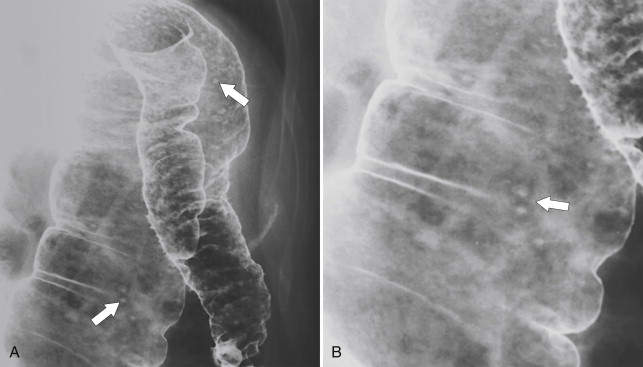

The imaging features are similar to those described in the small bowel, although the imaging of colonic Crohn disease can, at times, mimic those of UC. However, there are a number of distinguishing features that help to differentiate the two diseases ( Table 5-3 ). Plain radiography may demonstrate mucosal thickening ( Fig. 5-19 ) or toxic megacolon. Contrast enema studies (usually barium) may demonstrate involvement of the whole colon (which is therefore difficult to distinguish from UC), but this is uncommon. More commonly a variable segment of the colon is affected ( Fig. 5-20 , A ), and the disease may or may not involve the rectum. Acute disease at CT may present with mural stratification similar to that in the small bowel, representing mucosal and serosal hyperemia with submucosal inflammation or simple mural thickening and mesenteric edema ( Fig. 5-20 , B ). Aphthous ulceration is characteristic of Crohn disease ( Fig. 5-21 ). As in the small bowel, the mucosa in active disease enhances avidly after the administration of IV gadolinium. Although CT is easier and faster to perform, many patients with Crohn disease are young and may require repetitive assessment of the extent of their disease, so avoiding the radiation dose from multiple CT images is preferable. Therefore MRI is often advised, and newer MR enterographic techniques, particularly of the small bowel, have proved highly effective for evaluating the extent of disease ( Fig. 5-22 ). Furthermore, the extent of perianal disease is best imaged with MRI, which can outline the relationship of inflammatory disease to the internal and external anal sphincters; this is important to determine whether surgical repair is needed.

Figure 5-21, A, BE in a 36-year-old woman with numerous apthous ulcers ( arrows ) in the left colon from Crohn disease. B, Magnified view of apthous ulcers ( arrow ) in the distal transverse colon.